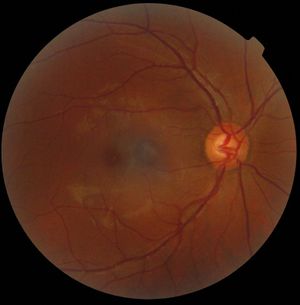

منظار العين Ophthalmoscopy جهاز بصري لفحص الجزء الداخلي من العين. وبإمكان أطباء العيون واختصاصيّي البصر تشخيص حالات كثيرة خاصة بالعين باستخدام منظار العين لفحص بعض الحالات الشاذة للعين.

يوجد نوعان من مناظير العين، هما: منظار العين المباشر ومنظار العين غير المباشر. يحتوي النوع المباشر على مصدر ضوء ومنشور ومرآة وعدسات. وتوضع هذه الأجزاء في مقدمة الجهاز المرتبط بمقبض يحتوي على بطارية. ويقوم المنشور والمرآة بتسليط الضوء على الجزء الخلفي من العين، بينما تمكِّن العدسات الفاحص من تبئير الضوء بحيث يستطيع رؤية صورة واضحة مكبرة للجزء الداخلي من العين. أما منظار العين غير المباشر فإنه يتألف من مصدر ضوء يوضع على رأس الفاحص وعدسة توضع أمام عين المريض. ويستطيع الفاحص بهذا الجهاز مشاهدة مساحة أوسع من التي يستطيع مشاهدتها بالمنظار المباشر ولكنها تكون مكبرة بنسبة أقل.